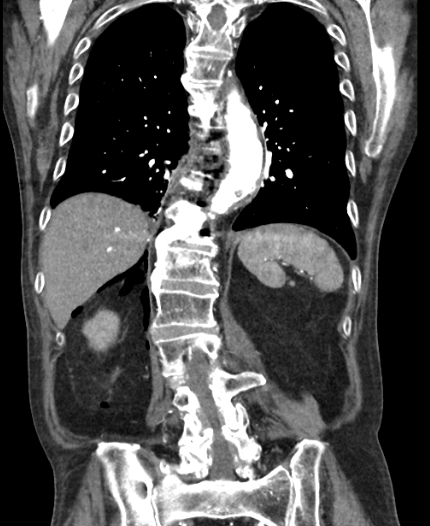

A 70 yo M presents to the ED with back pain s/p fall one day prior. The patient has a history of metastatic bladder cancer with known spinal mets. A CT chest/abdomen/pelvis is obtained. What's the diagnosis? (scroll down for answer)

Answer: Retroperitoneal Free Air (Pneumoretroperitoneum)

- Always considered an abnormal finding, and is uncommon compared to pneumoperitoneum

- Causes include: perforated retroperitoneal hollow viscus (duodenum, ascending/descending colon, rectum), residual air from retroperitoneal surgery, and trauma

- Best appreciated by CT scan, but can be detected by plain film

- Air most commonly seen surrounding kidneys in RUQ or LUQ of abdomen

- Requires prompt surgical exploration